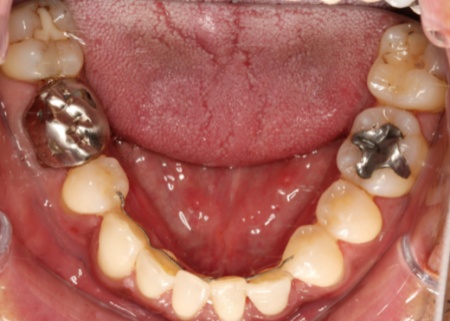

治療後

月に1回程度装置の調整のために来院いただいた結果、約3年で口元のバランスが整いました。

矯正治療後は歯並びが元に戻らないようにするため、上下前歯の裏側に保定装置を着用していただきながら、定期的なメンテナンスを続けています。